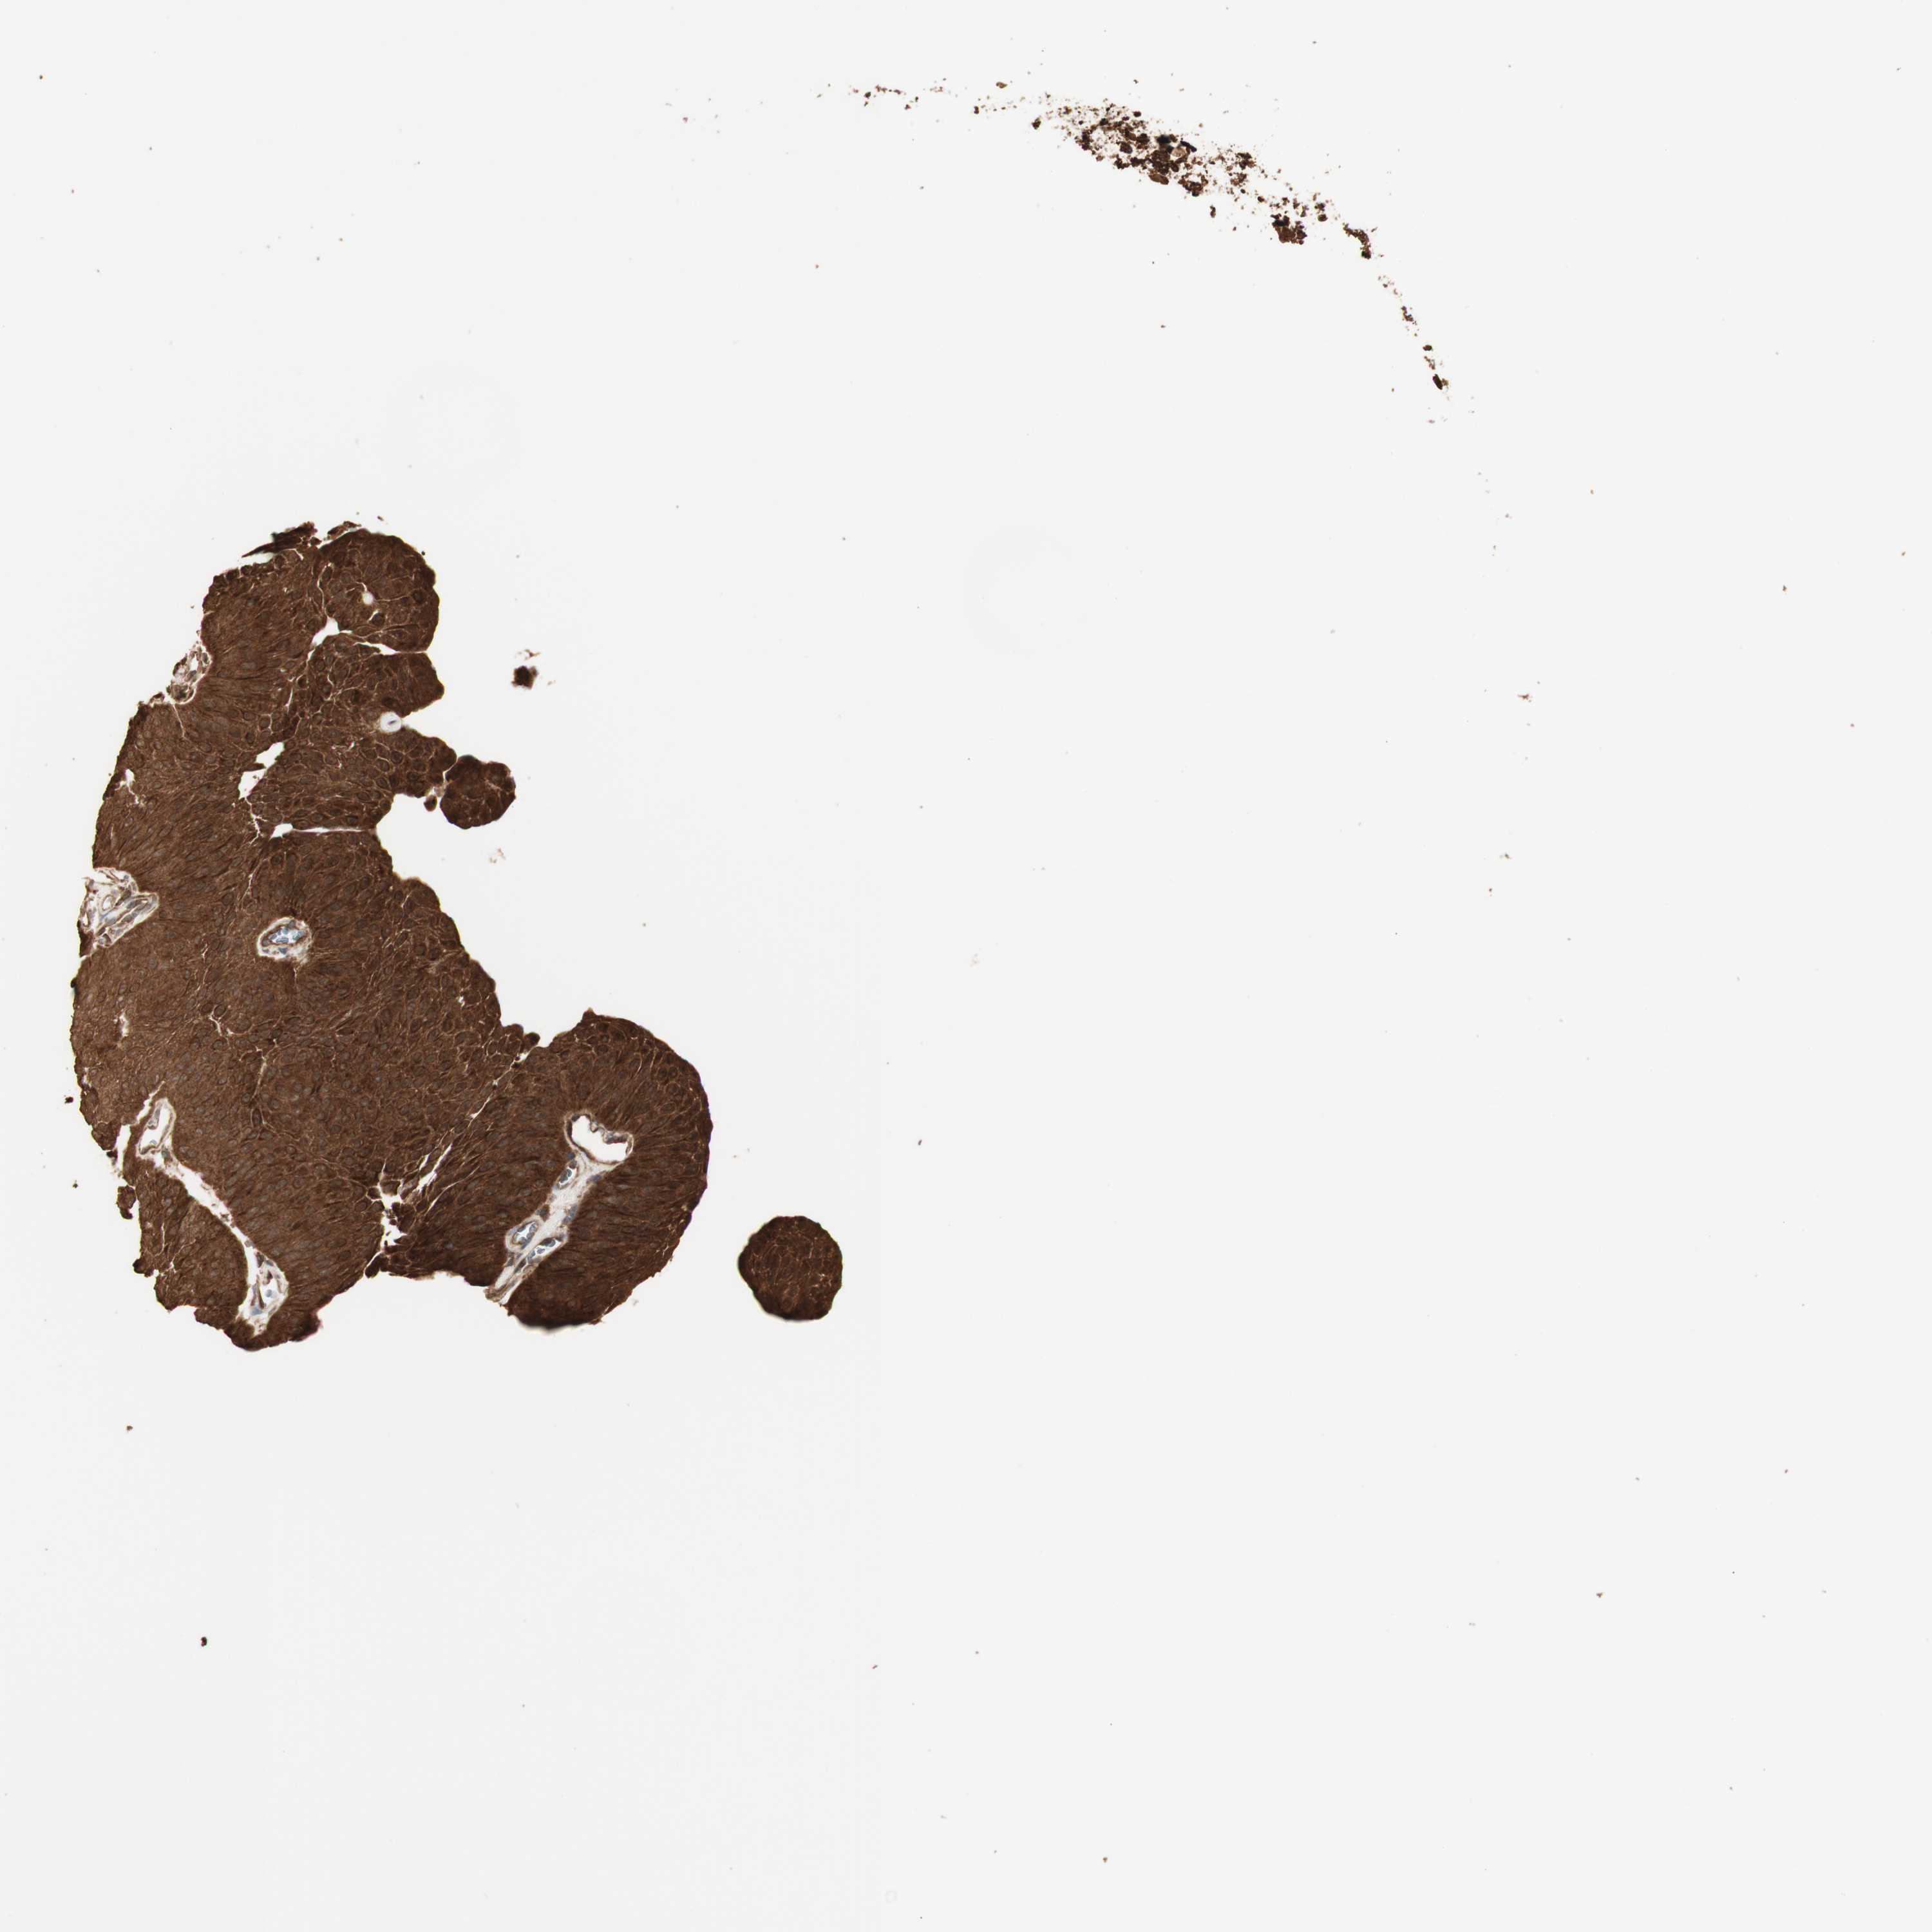

UROTHELIAL CANCER - Protein expressioni

A mouse-over function shows sample information and annotation data. Click on an image to view it in a full screen mode. Samples can be filtered based on level of antibody staining by selecting one or several of the following categories: high, medium, low and not detected. The assay and annotation is described here.

Note that samples used for immunohistochemistry by the Human Protein Atlas do not correspond to samples in the TCGA dataset.

Antibody stainingi

Antibody staining in the annotated cell types in the current human tissue is reported as not detected, low, medium, or high, based on conventional immunohistochemistry profiling in selected tissues. This score is based on the combination of the staining intensity and fraction of stained cells.

Each image is clickable and will lead to virtual microscopy that enables deeper exploration of all samples and also displays staining intensity scores, fraction scores and subcellular localization as well as patient and tissue information for each sample.

Antibody HPA007925

Antibody HPA011212

Antibody CAB003759

Antibody CAB080290

Urothelial carcinoma, Low grade

Urothelial carcinoma, High grade